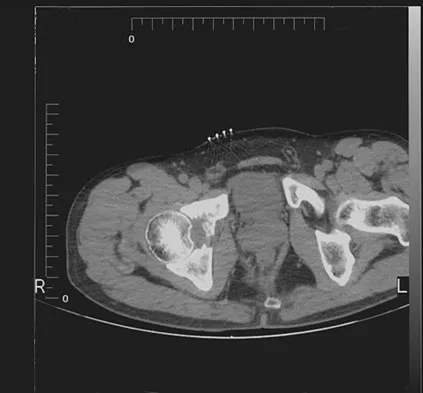

Which of the following findings best describes the acetabular fracture shown in Figure 38?

The CT scan shows a posterior wall fracture with impaction of the articular surface and a free fragment within the joint. Proper treatment of this injury requires not only reduction and fixation of the posterior wall fragment but also removal of the free fragment and elevation of the depressed articular segment. Letournel E, Judet R: Fractures of the Acetabulum, ed 2. Berlin, Germany, Springer Verlag, 1993.

A 46-year-old woman who was involved in a motor vehicle accident reports a 4-month history of right-sided lower back pain and pain radiating into the right thigh. The patient underwent an extensive 3-month course of physical therapy and now is dependent on narcotic medication for pain control. Epidural injection therapy has failed to improve her symptoms. Examination is significant for weakness of hip flexion in the seated position and for decreased sensation to light touch in the medial anterior thigh region. Straight leg raise is negative, but the femoral stretch test reproduces anterior thigh pain. A CT myelogram image, at L3-L4, is shown in Figure 3. What is the most appropriate management at this time?

The CT scan reveals a right-sided lateral disk protrusion at L3-4 that has been symptomatic for more than 4 months despite appropriate nonsurgical management. Relative surgical indications include persistent radiculopathy despite an adequate trial of nonsurgical management, recurrent episodes of sciatica, persistent motor deficit with tension signs and pain, and pseudoclaudication caused by underlying stenosis. Whereas studies have shown improvement in patients with sciatica from a lumbar disk herniation treated either nonsurgically or surgically, those undergoing surgical treatment had an overall greater improvement of symptoms. Weinstein JN, Lurie JD, Tosteson TD, et al: Surgical vs nonoperative treatment for lumbar disk herniation: The Spine Patient Outcomes Research Trial (SPORT) observational cohort. JAMA 2006;296:2451-2459.